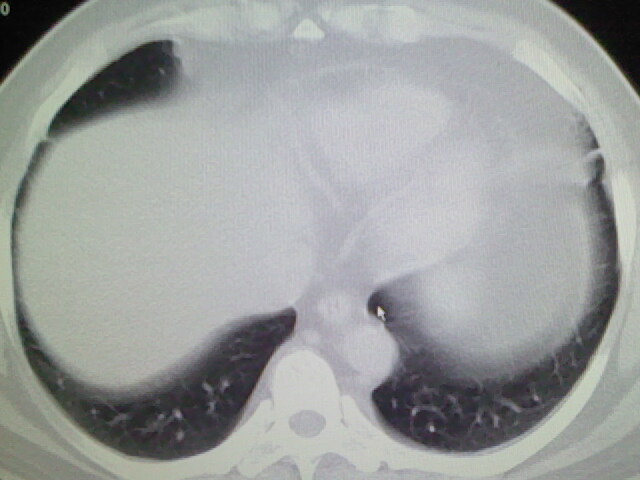

标题: CT17932:临床怀疑肺栓塞

男,34岁,自觉右侧胸痹,胸闷3天余

两肺纹理增多,余未见明确异常。

左肺上叶舌段少许炎症。

肺纹理分布较均匀,暂不提示肺梗塞

左上肺局限片状透光度增强区,肺纹理稀少,可考虑局限性肺气肿。

右侧肺动脉似见密度稍低影,请在机器的薄层上再看看有没有充盈缺损。

左上肺局限性肺透光度减低,肺纹理稀少;这虽然符合早期肺栓塞的改变,但与局限性肺气肿难以鉴别。

书上讲早期肺栓塞就是表现肺透光度减低,肺纹稀少。